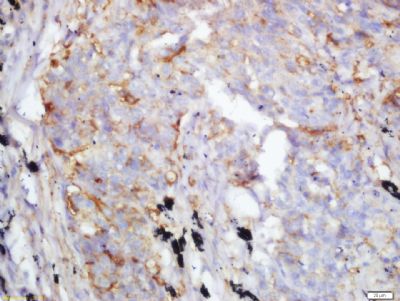

Fibrinogen beta chain,纤维蛋白原β链抗体产品应用WB=1:100-500 ELISA=1:500-1000 IHC-P=1:100-500 IHC-F=1:100-500 ICC=1:100-500 IF=1:100-500 (石蜡切片需做抗原修复)